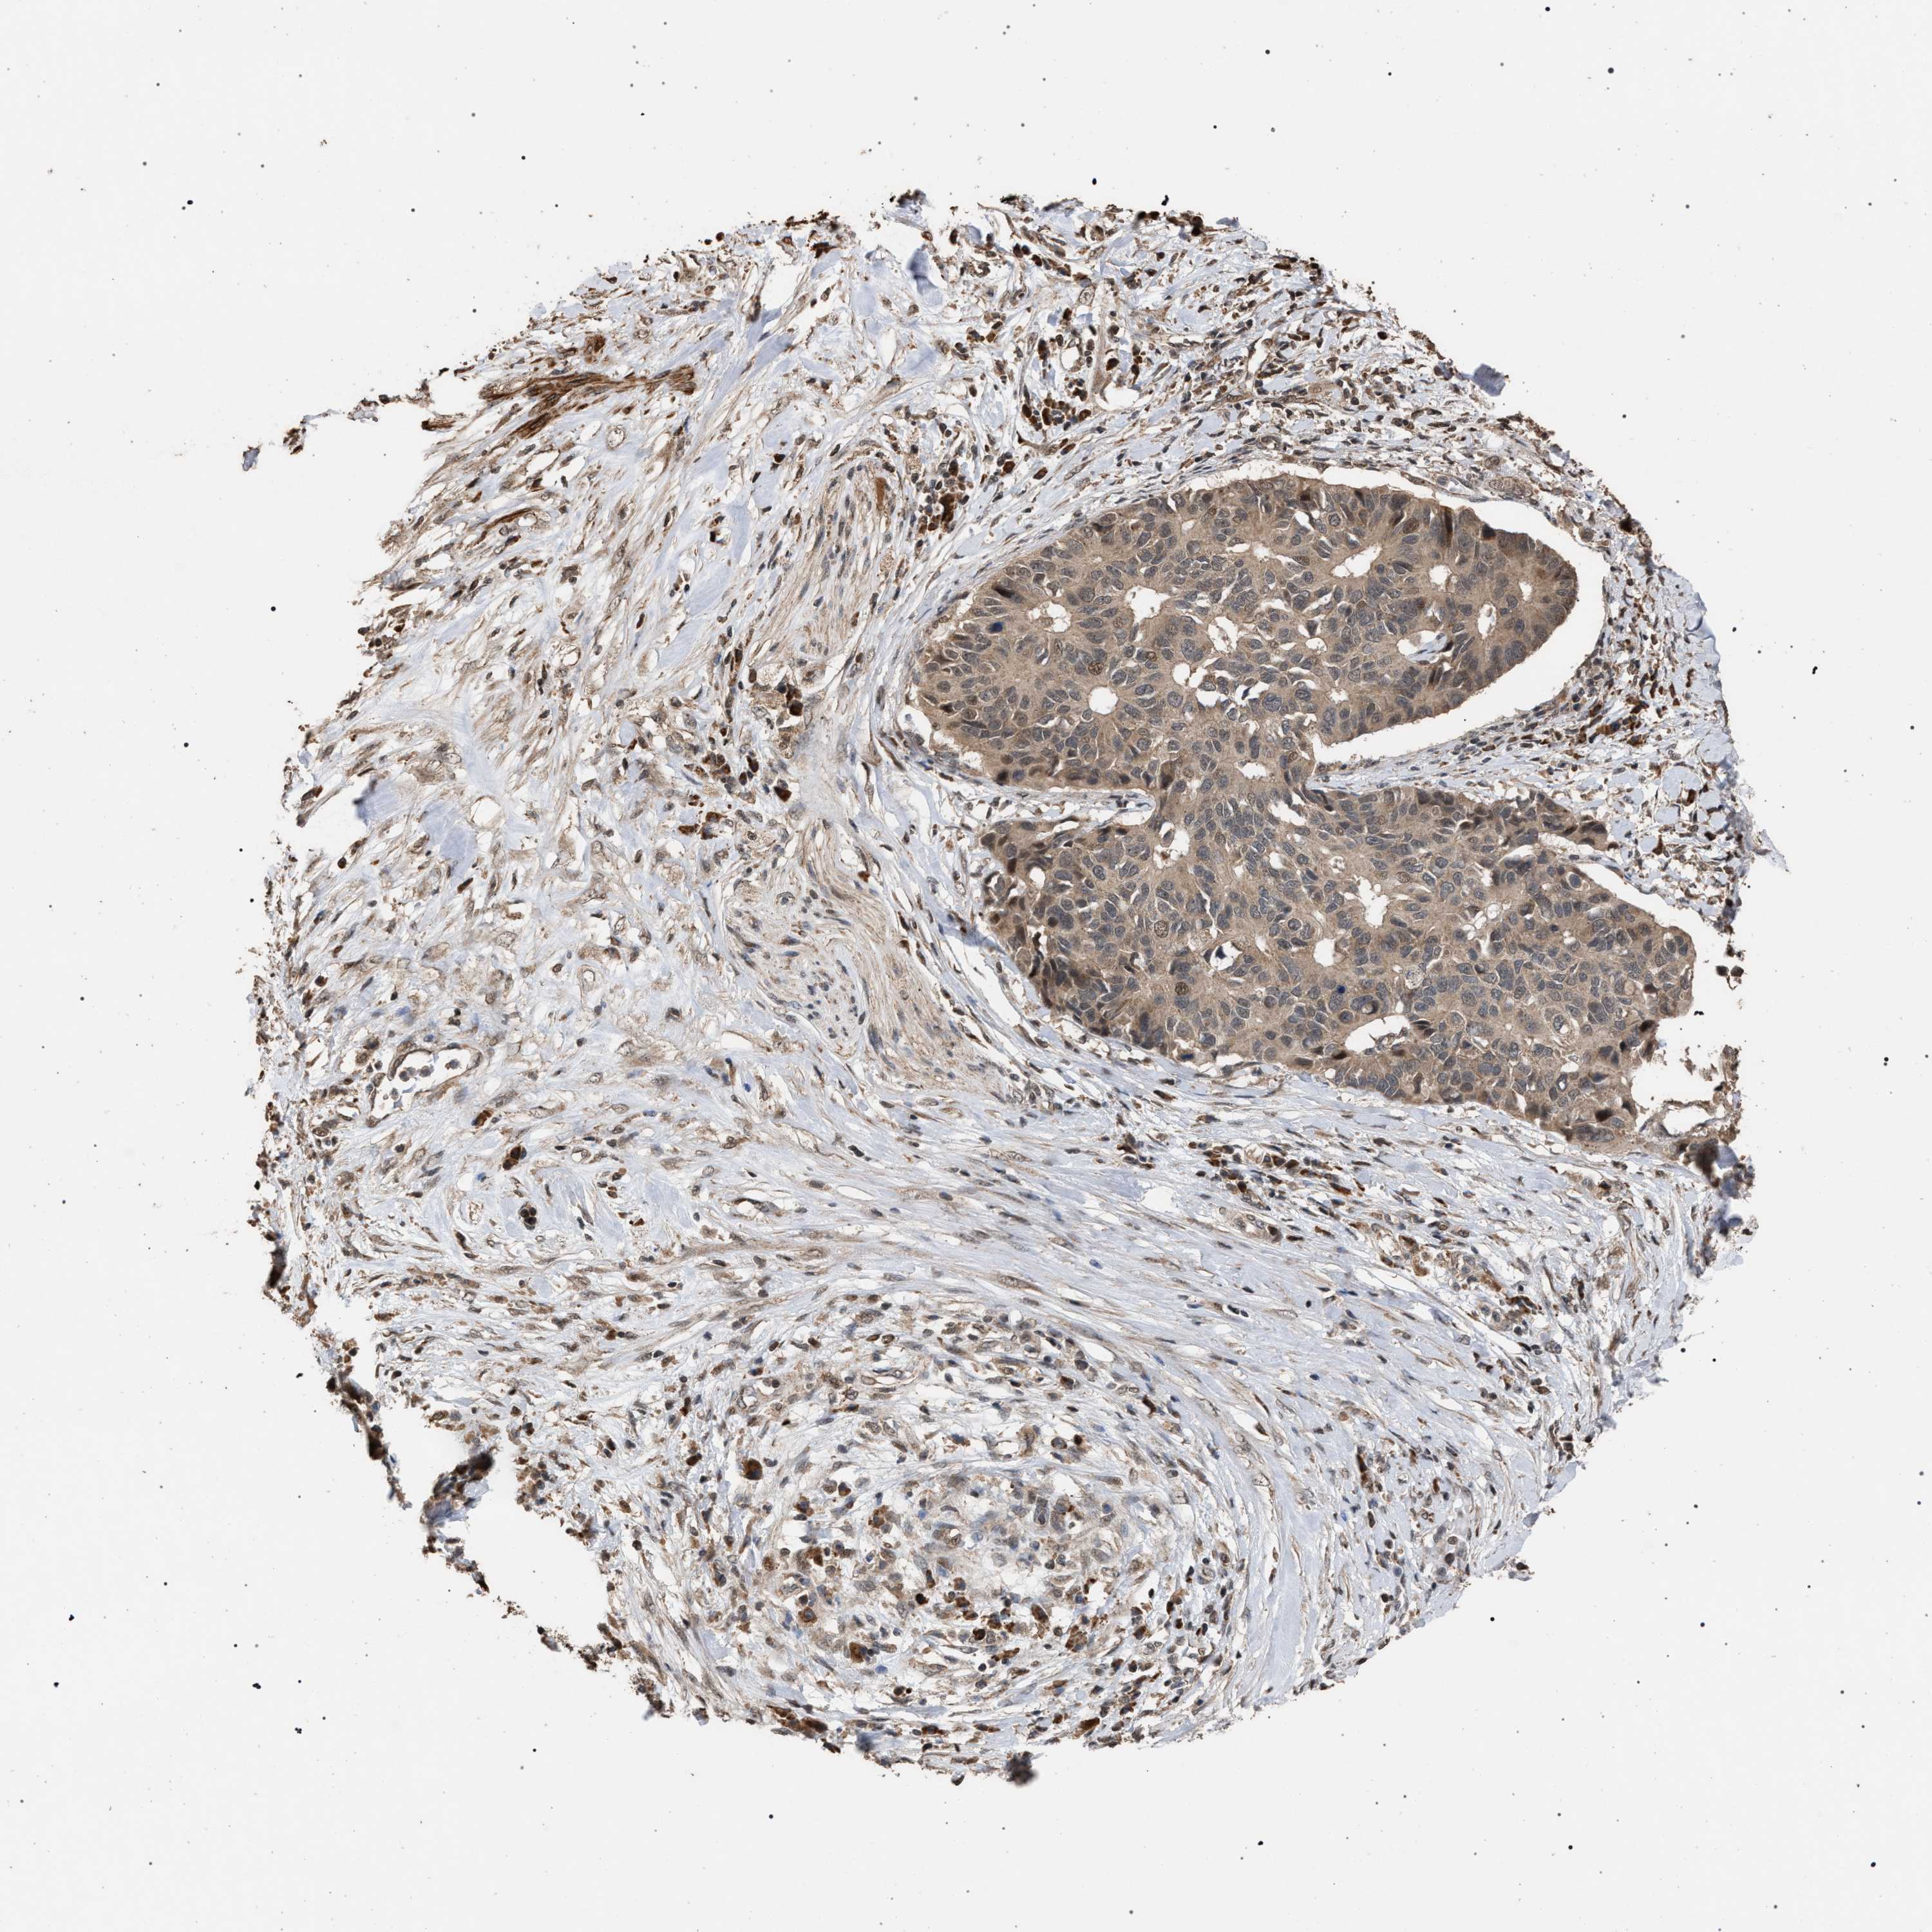

PANCREATIC CANCER - Protein expressioni

A mouse-over function shows sample information and annotation data. Click on an image to view it in a full screen mode. Samples can be filtered based on level of antibody staining by selecting one or several of the following categories: high, medium, low and not detected. The assay and annotation is described here.

Note that samples used for immunohistochemistry by the Human Protein Atlas do not correspond to samples in the TCGA dataset.

Antibody stainingi

Antibody staining in the annotated cell types in the current human tissue is reported as not detected, low, medium, or high, based on conventional immunohistochemistry profiling in selected tissues. This score is based on the combination of the staining intensity and fraction of stained cells.

Each image is clickable and will lead to virtual microscopy that enables deeper exploration of all samples and also displays staining intensity scores, fraction scores and subcellular localization as well as patient and tissue information for each sample.

Antibody HPA021547

Staining

High

Medium

Low

Not detected

Intensity

Strong

Moderate

Weak

Negative

Quantity

>75%

75%-25%

<25%

None

Location

Nuclear

Cytoplasmic/membranous

Cytoplasmic/membranous,nuclear

Adenocarcinoma, NOS